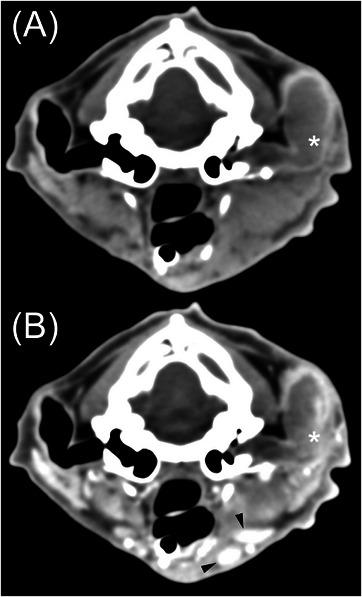

25只患有耳道肿瘤的猫的计算机断层扫描结果。

Computed tomographic findings in 25 cats with ear canal neoplasia.

Computed tomography is commonly used to evaluate feline otic disease; however, published studies characterizing the CT appearance of ear canal neoplasia are limited. The purpose of this multicenter, retrospective, secondary analysis, cross-sectional study was to describe the CT features of histopathologically confirmed feline ear canal neoplasia. The CT studies of 25 cats with ear canal neoplasia were prospectively scored by consensus of two veterinary radiologists. Recorded parameters were the presence of focal or multifocal tissue enlargement (mass/masses), lesion shape, location of the center of mass, attenuation characteristics, features of contrast enhancement, involvement of otic structures, calvarial and brain changes, changes of nearby structures, and lymphadenopathy. There was a significant overlap of CT findings between cats with malignant ceruminous gland neoplasia, ceruminous gland adenoma, and squamous cell carcinoma (SCC). Ceruminous gland adenoma was typically homogeneous in attenuation with homogeneous contrast enhancement and no intralesional fluid accumulations (IFAs) or involvement of adjacent structures. In contrast, SCC consistently had heterogeneous attenuation, heterogeneous contrast enhancement, IFAs, and involvement/invasion of adjacent structures. Malignant ceruminous gland neoplasia had variable attenuation and pattern of contrast enhancement with occasional IFAs and occasional involvement/invasion of adjacent structures. Knowledge of these imaging features will inform the creation of prioritized differential diagnosis lists. However, a biopsy is required to confirm the diagnosis.

摘要

计算机断层扫描常用于评估猫的耳部疾病;然而,已发表的关于耳道肿瘤CT表现特征的研究有限。这项多中心、回顾性、二次分析横断面研究的目的是描述经组织病理学证实的猫耳道肿瘤的CT特征。两名兽医放射科医生通过共识对25只患有耳道肿瘤的猫的CT研究进行前瞻性评分。记录的参数包括局灶性或多灶性组织增大(肿块)的存在、病变形状、肿块中心位置、衰减特征、对比增强特征、耳部结构受累情况、颅骨和脑部变化、附近结构变化以及淋巴结病。恶性耵聍腺肿瘤、耵聍腺腺瘤和鳞状细胞癌(SCC)的猫之间的CT表现存在显著重叠。耵聍腺腺瘤的衰减通常均匀,对比增强均匀,无瘤内液体聚集(IFA)或相邻结构受累。相比之下,SCC始终具有不均匀衰减、不均匀对比增强、IFA以及相邻结构受累/侵犯。恶性耵聍腺肿瘤的衰减和对比增强模式各不相同,偶尔有IFA,偶尔有相邻结构受累/侵犯。了解这些影像学特征将有助于制定优先鉴别诊断清单。然而,确诊需要活检。